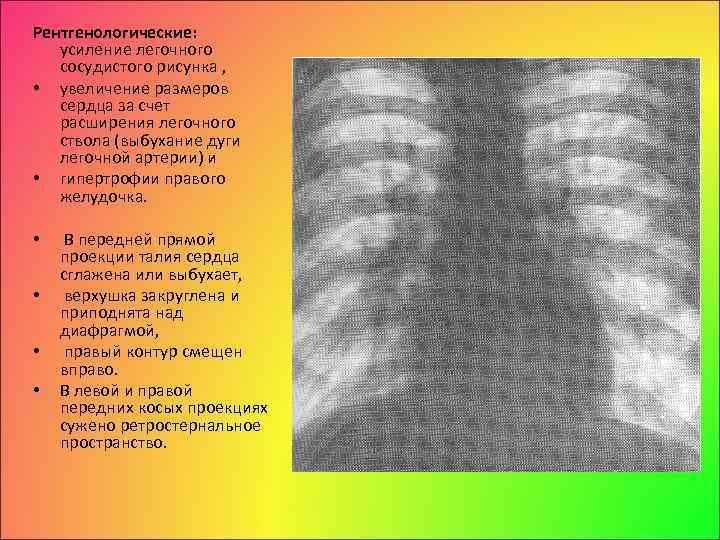

Усиление сосудистого рисунка легких на рентгене - это явление, которое может быть наблюдаемо при проведении рентгенологического исследования органов дыхания. В результате усиления сосудистого рисунка, на снимке становятся более заметными сосуды, расположенные внутри легких. Это может свидетельствовать о различных патологических процессах, таких как воспаление легких, обструкция дыхательных путей или сердечная недостаточность. Усиление сосудистого рисунка является важным признаком для постановки диагноза и выбора оптимального лечения. Однако, для точной интерпретации рентгеновского снимка необходимо учитывать и другие клинические данные, а также провести дополнительные исследования, если необходимо.